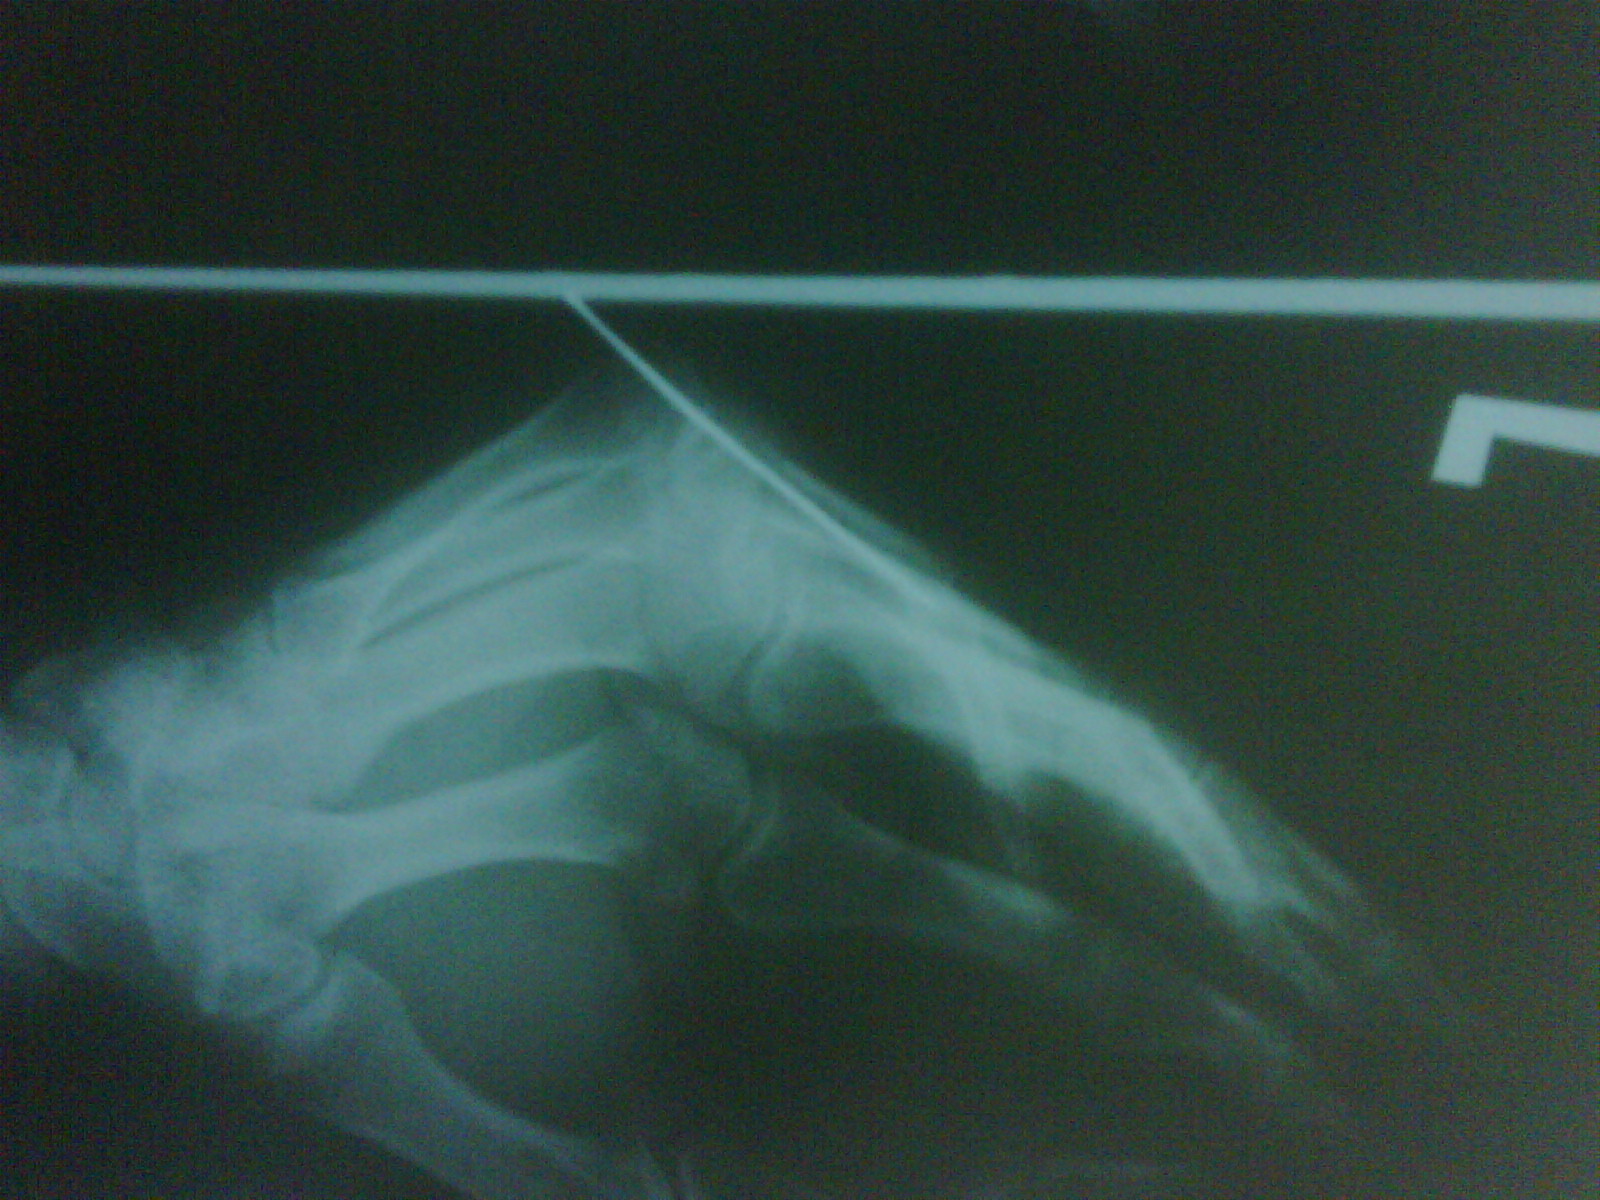

I need a bit of an opinion on a medical problem, I broke my small finger in the first bone just after the first joint, first time they plastered it and it was starting to set at like 45 degrees, so they put a wire in as shown in the xrays.

Now I have about 10 degrees flexion in each joint (all 3), this has been about 3 months now, the xrays taken today and pictures show you whats going on clearly enough where there is deformity in the first bone.

Thanks for the input, the axis of the small finger is like 30 degrees off to where it should be affecting all three joints and the next finger too, have broken more glasses from the weakness and habit of picking stuff up with out thinking.